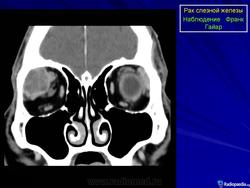

Диагноз устанавливают только после гистологического исследования. Предположительный диагноз может быть установлен на основании анализа клинических симптомов и результатов инструментального исследования. При рентгенографии на фоне увеличенной в размерах орбиты выявляются участки костной деструкции, чаще в верхненаружной, верхней и наружной стенках орбиты. Компьютерная томография позволяет определить протяженность тени опухоли, неравномерность ее краев, распространение в прилежащие экстраокулярные мышцы и неравномерность контуров костной стенки орбиты или ее полное разрушение, а ультразвуковое исследование — лишь наличие тени опухоли и ее плотность. Радиосцинтиграмма орбиты при аденокарциноме характеризуется увеличением коэффициента асимметрии, свойственного злокачественным опухолям. Информативна дистанционная термография, особенно с сахарной нагрузкой. Уточнить диагноз помогает дооперационная тонкоигольная аспирационная биопсия.